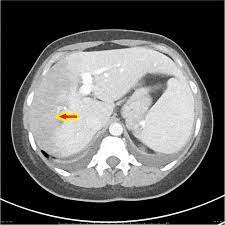

Chiasmata -mə-tə or chiasmas also chiasms 1. Esophageal varices are extremely dilated sub-mucosal veins in the lower third of the esophagus. Located in metro Denver northern Colorado and western Nebraska serving all of the Front Range our team consists of board-certified and fellowship-trained interventional radiologists. This results in hepatic congestion similar to Budd-Chiari syndrome and post-sinusoidal portal hypertension. The patients condition should be monitored throughout the procedure. They are most often a consequence of portal hypertension commonly due to cirrhosis. Toxic injury to liver sinusoids causes sloughing of endothelial cells that embolize to hepatic venules and cause eventual fibrosis of the venules. Coin in the Esophagus. There is no clear consensus regarding the number of occluded veins some authors claim that there should be at least one occluded hepatic vein 7 others state that there are no significant.

Carcinoma of the Colon. Budd-Chiari syndrome a blockage in one or more veins that carry blood from the liver back to the heart. And coumarin skin necrosis adrenal gland hemorrhage and infarction. Toxic injury to liver sinusoids causes sloughing of endothelial cells that embolize to hepatic venules and cause eventual fibrosis of the venules. Chiari malformation CM is a structural defect in the cerebellum characterized by a downward displacement of one or both cerebellar tonsils through the foramen magnum the opening at the base of the skull. Embolism and thrombosis of. La présence dune ou plusieurs affections prothrombotiques est fréquente La prise en charge repose sur un traitement anticoagulant précoce le traitement de l.